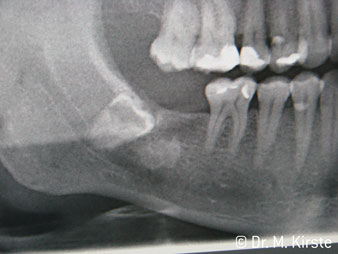

La conception particulière des roulements à l'intérieur de la tête du contre-angle garantit un fonctionnement silencieux de l’instrument rotatif et lui procure une grande efficacité de coupe, sans à-coup ; ce qui est appréciable lors des interventions chirurgicales comme par exemple les séparations dentaires et résections apicales (Ill. 4-9).

Ill. 4